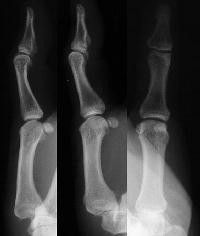

Preoperative films.